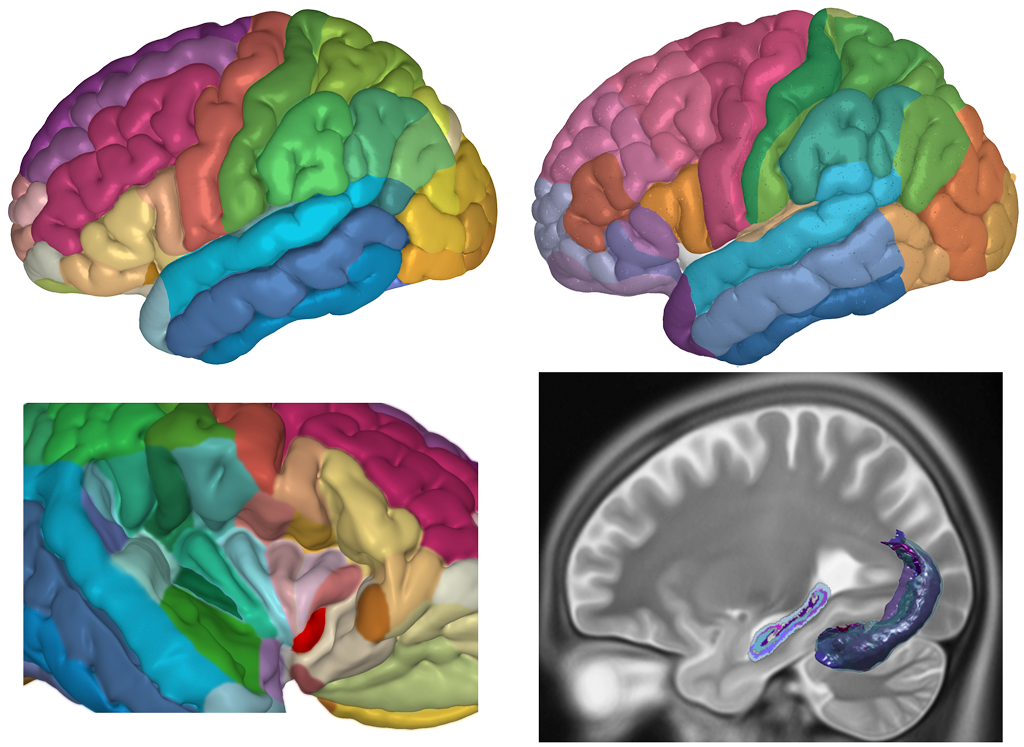

CORTEX

• Detailed sulco-gyral Cortex Designations

• Brodmann Areas delineated

Each drawing in the atlas shows the delineation of individual anatomical structures representing their cross-sectional area of the corresponding 3D model.